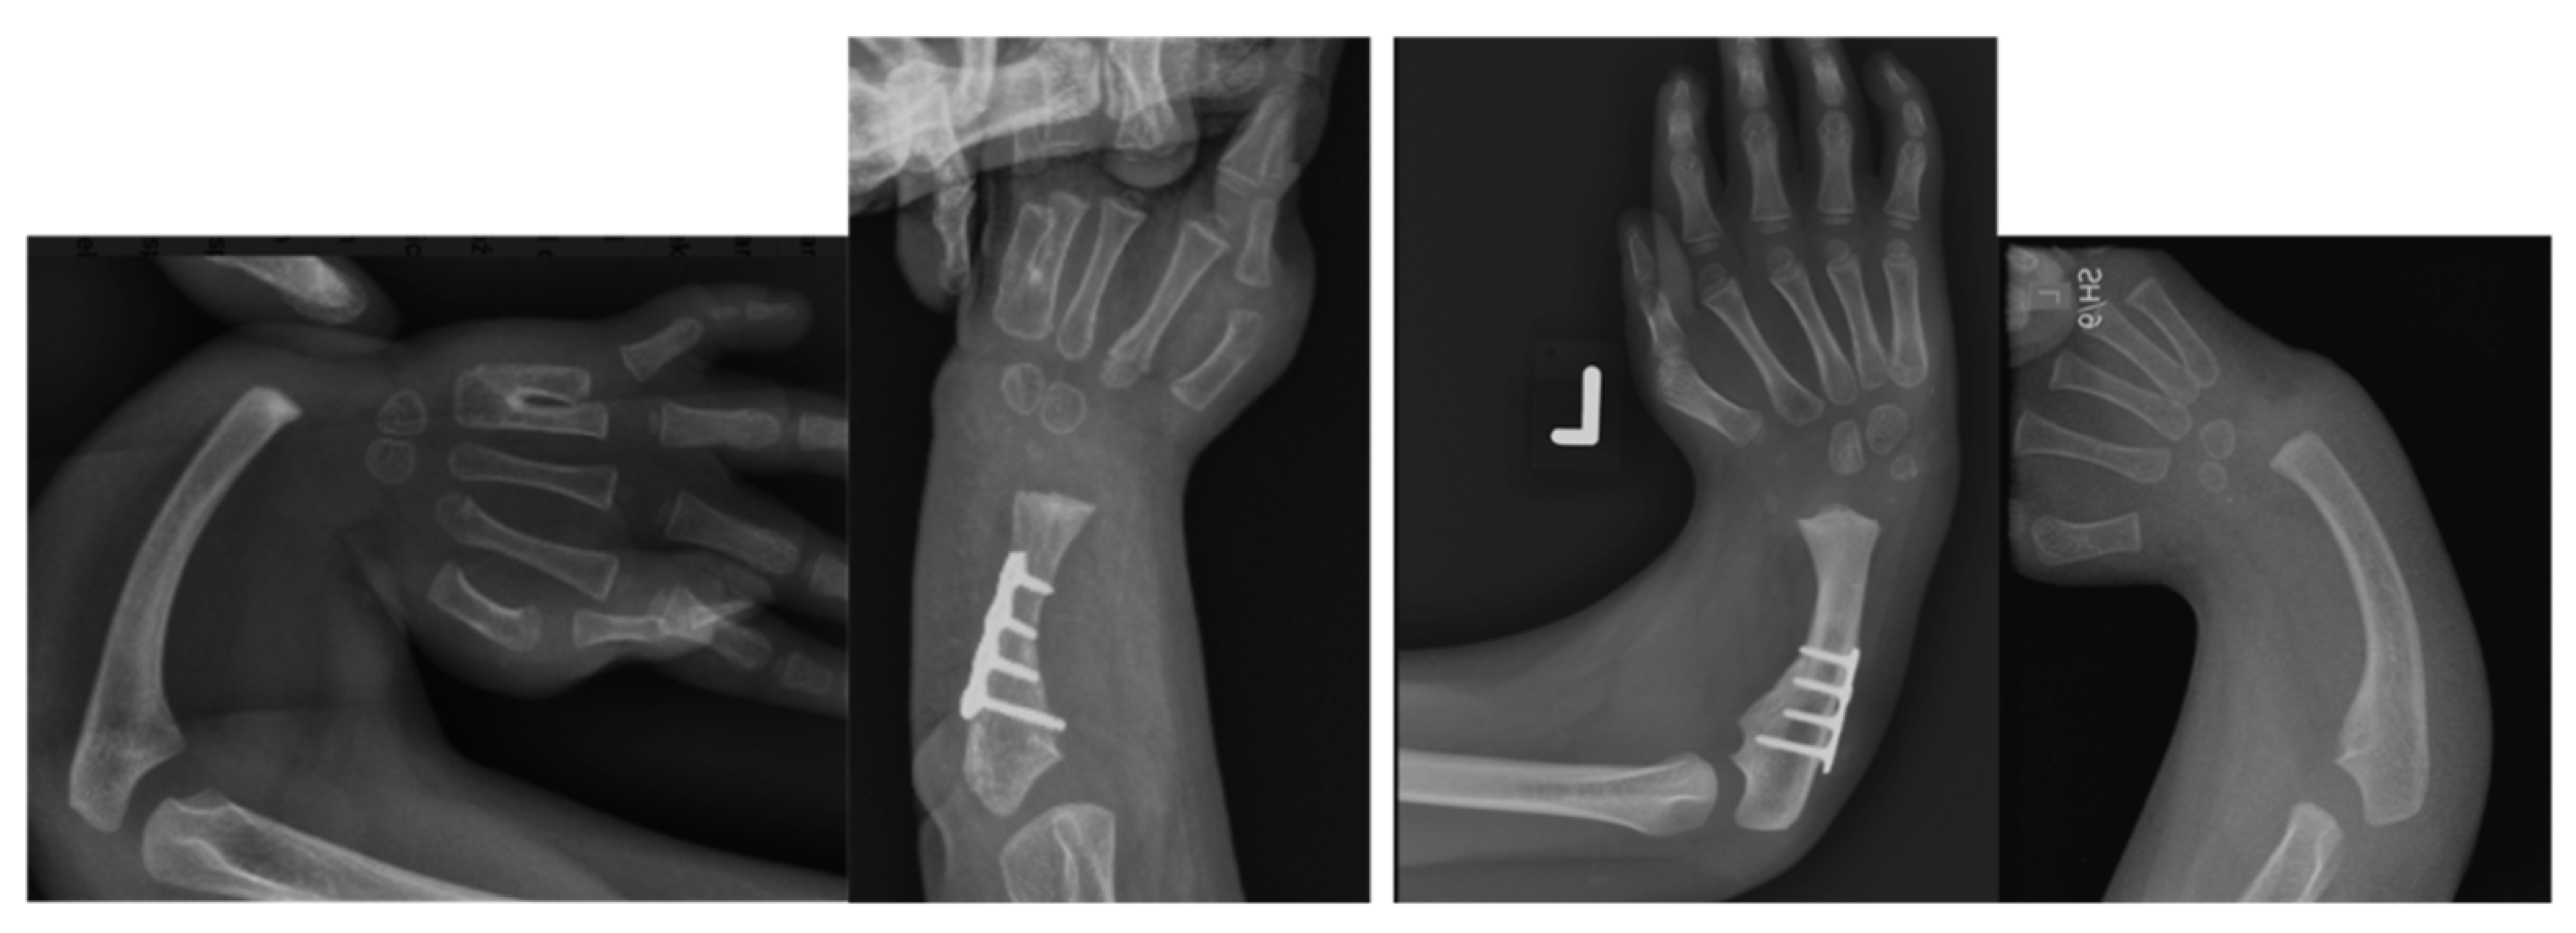

Figure 4.

Case 9 left, 10 right. Bilateral RCH preop radiographs (left most, right most). Postop radiographs after ulnarization G3 of both hands (left middle, right middle). Note the hypertrophy of the head of the ulna after surgery in both hands.